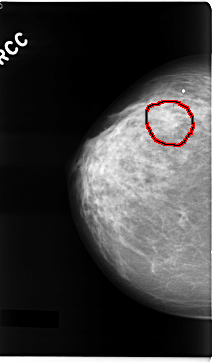

C_0041_1.RIGHT_CC

RIGHT_CC LINES 4704 PIXELS_PER_LINE 2768 BITS_PER_PIXEL 12 RESOLUTION 50 OVERLAY

FILE: C_0041_1.RIGHT_CC.OVERLAY

TOTAL_ABNORMALITIES 1

ABNORMALITY 1

LESION_TYPE MASS SHAPE IRREGULAR MARGINS ILL_DEFINED

ASSESSMENT 4

SUBTLETY 3

PATHOLOGY MALIGNANT

TOTAL_OUTLINES 1

BOUNDARY